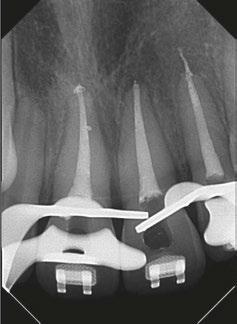

sistence of apical periodontitis. The purpose of an access cavity is to offer the clinician a proper entry into the pulpal chamber, the canal orifices, and into the canals all the way to the working length. It should allow the easy way-in and way-out of all the mechanical and chemical armamentarium during a root canal treatment.11

Traditionally, the endodontic access cavity was designed in a way that aimed to remove any obstruction in the way of reaching the canal orifices. This included the complete unroofing of the chamber, exposing all pulp horns, and obtaining a straight-line access to the apex — avoiding the need to alter visual angulation. This design also aimed at reducing the likelihood of iatrogenic errors.

There are various factors that influence the size of such cavities, notably the anatomical location of the orifices and visualizing these orifices without tilting the mirror.12 This results in an access cavity that is widest occlusally and smallest at the level of the orifices.12,13 Hence the drawback of such access cavity design is that it requires the removal of healthy tooth structure, specifically the pericervical dentin — the dentin present 4 mm above and 6 mm below the crestal bone which helps to distribute any forces placed on the tooth (Figure 1).14 This access design, known as Traditional Endodontic Cavity (TEC) is presently being questioned, giving rise to various access designs emphasizing the preservation of this pericervical dentin.14,15

Conservative Endodontic Cavity (Figure

2A)

The Conservative Endodontic Cavity (CEC) is a first step towards a less invasive access cavity while executing a root canal treatment. It is based on the partial deroofing of the pulpal chamber while preserving pulpal horns, resulting in a slight occlusal convergence. This elimination of straight-line access makes orifices visible one at a time using different visual angulation.16

It has been shown that CEC might increase the strength of endodontically treated teeth especially in mandibular premolars and molars.17 However, there are concerns about the ability of effective chemo-mechanical debridement and disinfection of the root canal system as well as procedural errors due to reduced direct vision.18

Ultraconservative Endodontic Cavity (Ninja) (Figure

2B)

The Ultraconservative Endodontic Cavity (UEC), also known as Ninja access, is a more minimalistic version of the CEC. It is performed by creating a cavity in the occlusal surface starting from the central fossa or incisal edge and reaching the pulpal floor with an extremely conservative deroofing of the chamber and preservation of the pulp horns. No further extension is made.15 This results in a super convergent cavity and the preservation of not only percervical dentin but also occlusal enamel. This ultraconservative shape makes it more challenging to locate, clean, disinfect, and obturate the root canal system. It also increases the risks of missed canals which can then lead to failure of the treatment. The increased mechanical stability and increased long-term survival claimed to be attributes to such cavity design are limited and debatable.17 There is also increased treatment time to be considered.

Truss Access Cavity (Figure

2C)

In the discussion of smaller access cavities with the aim of preserving pericervical dentin, we include the Truss Access Cavity. This design yields separate access cavities on the occlusal surface, aligned with the corresponding canals, to expose the orifices and leaving the truss of dentin intact in between.19